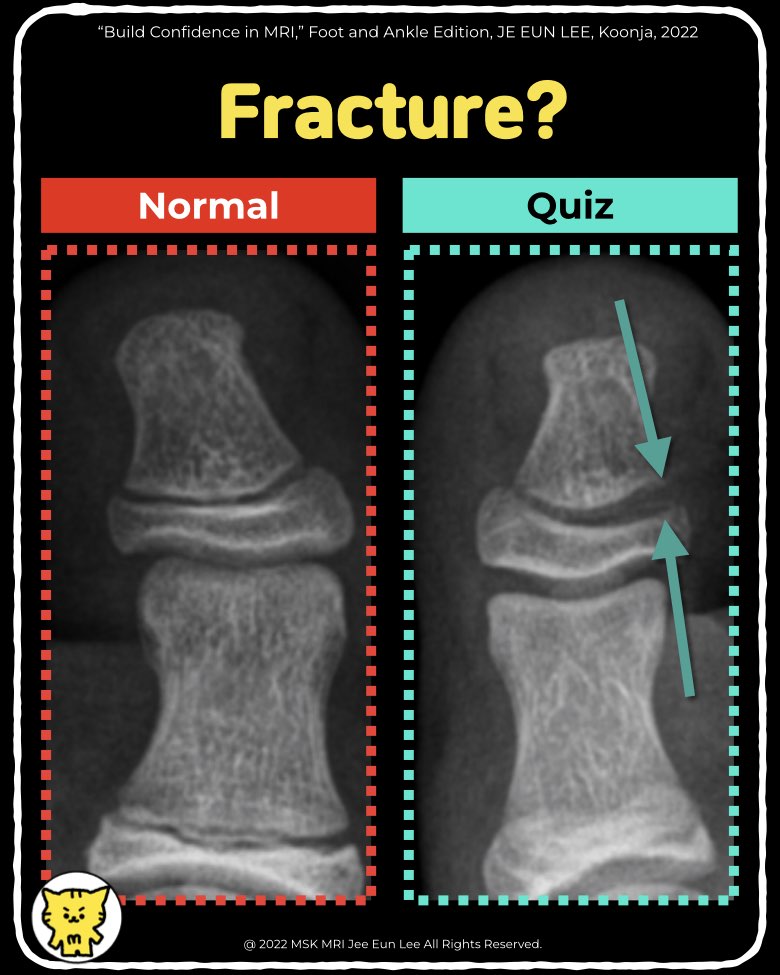

✔️Salter-Harris Type I Fracture of the Distal Phalanx

- Salter-Harris Type I fractures involve a fracture through the growth plate (physis) without bone involvement, often challenging to detect on radiographs. MRI is valuable for assessing physeal injuries, especially when radiographs are inconclusive.

- Fracture Location: The fracture occurs through the physis only, sparing the epiphyseal and metaphyseal regions.

- Fracture Fragments: Unlike other types, there are no discrete fracture fragments visible.

- Deformities: These fractures can present with angulation, displacement, or rotation, depending on the mechanism of injury.